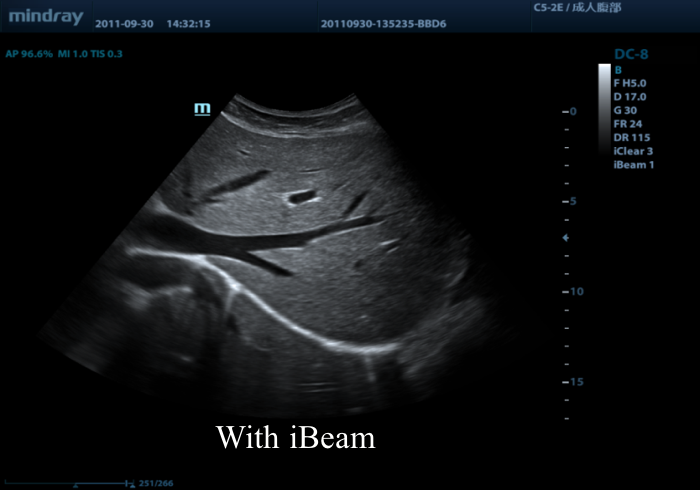

Данная технология представлена практически у каждого производителя ультразвуковой диагностической медицинской техники. У компании GE, данная технология поставляется под наименованием CrossBeam, у Mindray – iBeam, Siemens – Advanced SieClear, Philips – SonoCT, Esaote – Mview и т.д. Как и в случае с множеством других технологий, применяемых в ультразвуковом аппарате, здесь мы также имеем дело с одной и тойже технологией компаундинга. Различия в названиях на 99% - маркетинговый ход, и на 1% отличия для возможности запатентовать именно свою, брендованную технологию компаундинга (здесь стоит пояснить, что это сугубо наше мнение).

На практике, применение технологии многолучевого составного сканирования (компаундинга) давно стало стандартом. Сегодня, практически все производители включают данный режим в базовый комплект поставки прибора, а причина этого очень проста – это именно та технология, которая позволяет нам значительно уменьшить акустические тени и увеличить контрастное разрешение.

Принцип работы многолучевого составного сканирования (компаундинга) заключается в объединении кадров, полученных при генерации ультразвука под разными углами.

Предлагаем вам ознакомиться с примером применения данной технологии. Изображения выполнены на приборе Mindray DC-8, на верхнем изображении режим iBeam (компаундинг) отключен, а на нижнем включен на первую ступень регулировки (3 луча).